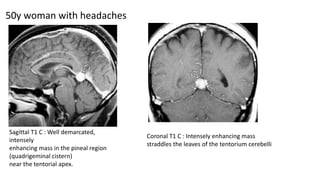

50y woman with headaches

Sagittal T1 C : Well demarcated,

intensely

enhancing mass in the pineal region

(quadrigeminal cistern)

near the tentorial apex.

Coronal T1 C : Intensely enhancing mass

straddles the leaves of the tentorium cerebelli

Tentorial apex meningioma